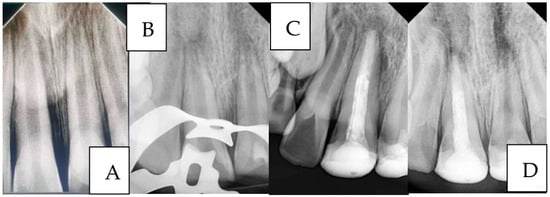

Case 2 (Figure 5):

A 7-year-old child presented to the Department of Pediatric Dentistry three days after the injury with a complicated crown fracture involving pulp exposure in tooth #42. Radiographic examination revealed that the fractured crown fragment was embedded within the lower lip. As the tooth had a closed apex, the fragment was surgically removed from the lip, followed by traditional endodontic treatment of tooth #42 in the same visit. The fractured crown segment was successfully reattached, restoring the tooth’s original form and function.

Figure 5. A case of managing a complicated crown fracture with the fractured fragment retained within the lower lip: (A): Preoperative view, (B): Radiograph showing the location of the broken fragment within the lower lip, (C): Surgical removal of the fractured fragment, (D): Isolation, endodontic treatment, and reattachment of the broken fragment in a single visit, and (E): 6 months follow-up.

Figure 6. A case of managing anterior teeth with a history of repeated trauma: (A): Diagnostic radiograph, (B): Radiograph showing working length determination for tooth #11 and MTA pulpotomy for tooth #21 (C): Radiograph showing the placement of MTA apical plug and final restorations, and (D): Two-year follow-up radiograph showing successful treatment outcome of tooth #11 and failure of tooth #21.

Case 3 (Figure 6):

A 9-year-old child presented to the Department of Pediatric Dentistry with a history of recurrent dental trauma. The first injury, one year prior, had resulted in an uncomplicated crown fracture of tooth #11, still untreated. In contrast, the second trauma, one month earlier, caused an uncomplicated crown fracture of tooth #21. The child’s main complaint was pain associated with tooth #21. Routine radiographic examination revealed pulp necrosis in tooth #11. Vital pulp therapy with MTA was performed on tooth #21, whereas tooth #11 was managed with an MTA apical plug.

A two-year follow-up radiograph showed a marked reduction in the apical radiolucency of tooth #11 and the formation of a mineralized apical barrier adjacent to the plug. In contrast, tooth #21 later developed symptoms of acute apical periodontitis, necessitating additional endodontic intervention.